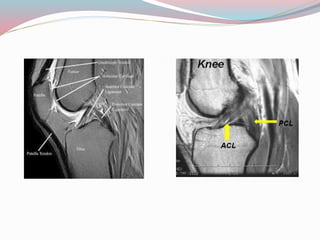

Knee injury

๏‚— MRI indicated to study the integrity of

cruciate & collateral ligaments, hyaline

cartilage menisci capsule any marrow edema

๏‚— Useful when plain x rays are non contributory

but patient has pain during locking and

unlocking movements

Knee injury ๏‚— MRIindicated to study the integrity of cruciate & collateral ligaments, hyaline cartilage menisci capsule any marrow edema ๏‚— Useful when plain x rays are non contributory but patient has pain during locking and unlocking movements